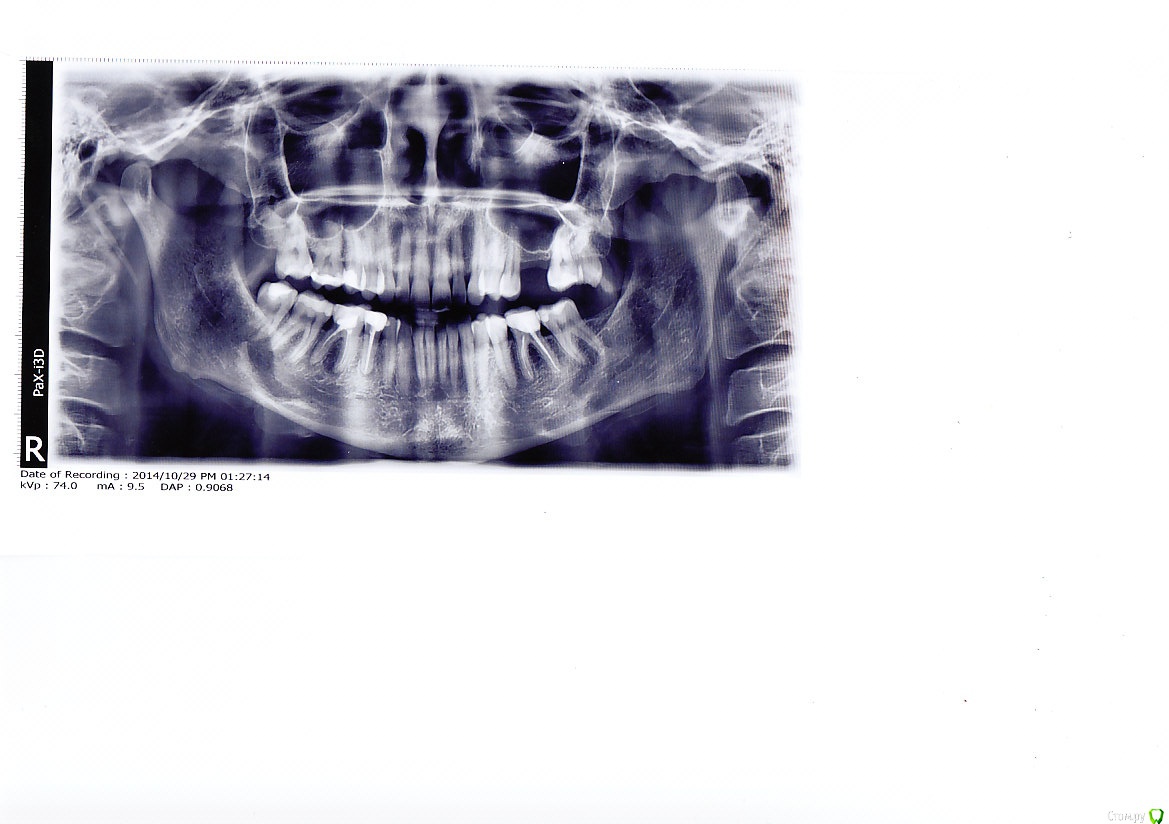

Немного пред истории, до всех манипуляций с зубами ничего не беспокоило .кроме отсутствия верхней 6-ки.На консультации у ортопеда выяснилось,что пора менять все пломбы (просели)и ставить коронки как минимум на 2 нижние 6-ки+ синуслифтинг и имплант.

Снимок сделан до всех манипуляций.

Что уже сделано, перелечили каналы в 36 и 46 зубах.Установлены культевые вкладки,металл.Какой сплав не знаю.

На 27.45,47,14.15,16.17.37 рекомендует  поставить вкладки из пресс-керамики. Согласны Вы по поводу объемов лечения и материалов?